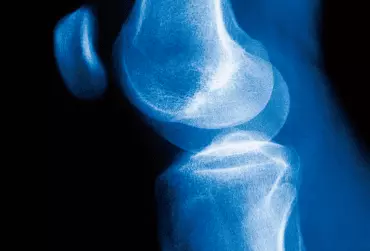

Szacuje się, że obrażenia stawu kolanowego stanowią 15–30% wszystkich uszkodzeń ciała, w urazach sportowych odsetek ten wzrasta od 33–70%. Wykluczając sportowców, urazy tkanek miękkich dotyczą często również osób nieaktywnych fizycznie i osób starszych [1–3].

Rehabilitacja po operacyjnym leczeniu łąkotki stawu kolanowego

Łąkotki stawu kolanowego to dwie włóknisto-chrzęstne struktury, których zadaniem jest pogłębienie i wypełnienie powierzchni stawowej. Charakteryzują się półksiężycowatym kształtem. Obrażenia łąkotek stawu kolanowego występują zazwyczaj u młodych ludzi uprawiających sport. U osób starszych, u których struktura łąkotek jest zazwyczaj osłabiona, do ich uszkodzenia może dojść nawet podczas codziennych czynności, np. przysiadu.

Postępowanie rehabilitacyjne po implantacji łąkotki poliuretanowej

Urazy łąkotek są jednymi z najczęstszych urazów stawu kolanowego, co potwierdza liczba interwencji chirurgicznych wykonywanych rocznie zarówno w Stanach Zjednoczonych (ok. 1 mln), jak i w Europie (ponad 400 tys.) [1]. Dotychczas jedyną możliwością leczenia uszkodzeń łąkotki, które nie nadawały się do zszycia, było wykonanie przeszczepu od martwego dawcy. Naukowcom jednak udało się opracować implant, tzw. łąkotkę poliuretanową.

Współczesne poglądy na temat leczenia operacyjnego i nieoperacyjnego zerwanego więzadła krzyżowego przedniego kolana

Temat uszkodzenia więzadeł krzyżowych przednich stawu kolanowego (anterior cruciate ligament – ACL) jest tym popularniejszy, im popularniejszy staje się sport masowy. Leczenie tej kontuzji sportowej budzi od jakiegoś czasu wiele kontrowersji – operować czy nie operować? Zagadnienie to nie jest już w Polsce niszowe, bo mowa tu o kilkudziesięciu tysiącach kontuzji kolan rocznie. Patrząc na statystyki krajów bardziej usportowionych, z dużym dostępem do specjalistów, np. Stanów Zjednoczonych, można zauważyć, że liczba rekonstrukcji więzadeł krzyżowych sięga 100 000 rocznie. Warto więc ustalić, jakie są współczesne poglądy na temat rekonstrukcji ACL.